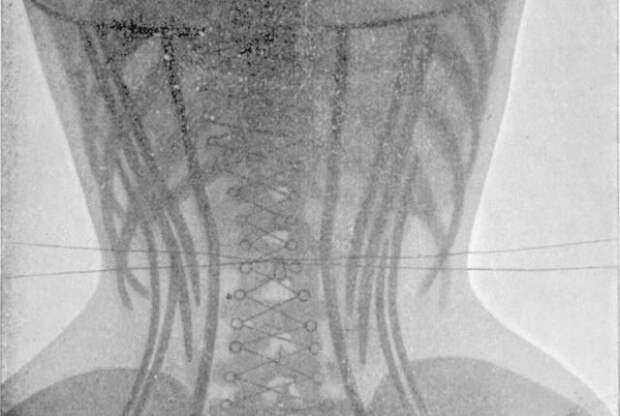

1. Корсеты

Пышущий здоровьем женский организм, вот что! Зачем, вы думаете, в 19 веке сильный пол с таким усердием охотился на китов? Чтобы женщины могли утягивать свои тела корсетами из китового уса и калечить внутренние органы, конечно.2. Мышьяк